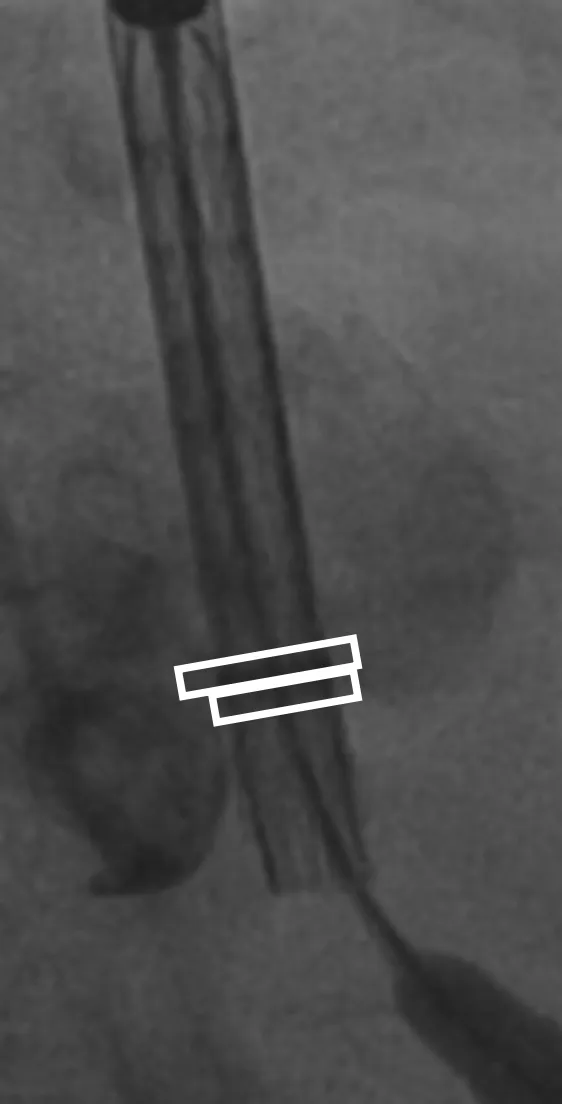

患者病史 男性,74y, 因 “发现心脏瓣膜病 1 年,加重伴喘气半年” 入院。门诊检查显示主动脉瓣重度AS并伴轻-中度AR。患者基础疾病较多:胸腹主动脉多发穿透性溃疡、心功能III级等,手术指征明确,但风险极高。 术前CT LVOT- Annulus 倒梯形,对植入瓣膜有挤压位移风险,Annulus直径23.7mm,瓣叶增厚,钙化集中在无冠窦边缘。 左冠脉开口高度可,瓣叶不长、窦部空间较大,无冠脉风险;室间隔膜部较短,有一定PPI风险,心脏角度37.9°;心室较小,有一定循环崩溃风险,术前注意补液。 术前造影角度及入路:血管入路散在钙化、无迂曲;主动脉弓条件好、双侧股动脉直径大、右股穿刺点侧壁存在环形钙化 左右重合位:RAO 7° CAU 21° 右窦中心位:LAO2 1° CAU 1° 手术策略 20mm球囊预扩后植入AV26瓣膜,同时做好预防循环崩溃、传导阻滞的应急预案。 术中挑战 1)球囊预扩:20mm球囊预扩时无明显 “腰征”,但存在少量反流,提示瓣膜钙化与解剖结构对扩张的阻力不均 2)首次释放偏差:第一次定位释放时,瓣膜在 “开花” 过程中下滑约 3mm,工作位观察显示小弯侧瓣周漏较多(深度超过完全覆膜区),需二次调整。 3)二次精准定位:以猪尾导管为参照,将定位点调整至 “猪尾 - 2mm” 处,结合真实窦底深度(较深)重新释放,最终瓣膜位置稳定,瓣周漏显著减少。 术后即刻效果: 瓣膜形态良好,跨瓣压差从术前的 67mmHg 降至 6mmHg,且无明显瓣周漏,冠脉开口通畅; Commisural Alignment 术后即刻超声: Prostyle A®预装干瓣——助力临床最优化解决方案: √ 平衡的径向支撑力:特殊的解剖结构下位置形态良好,术后跨瓣压差大幅降低,血流动力学改善明显; √ 80%可回收设计:支持术中二次调整释放位置,保证精准释放; √ 平衡的收腰设计&Commissural Alignment设计: 为患者后期冠脉PCI保留了生命通道;